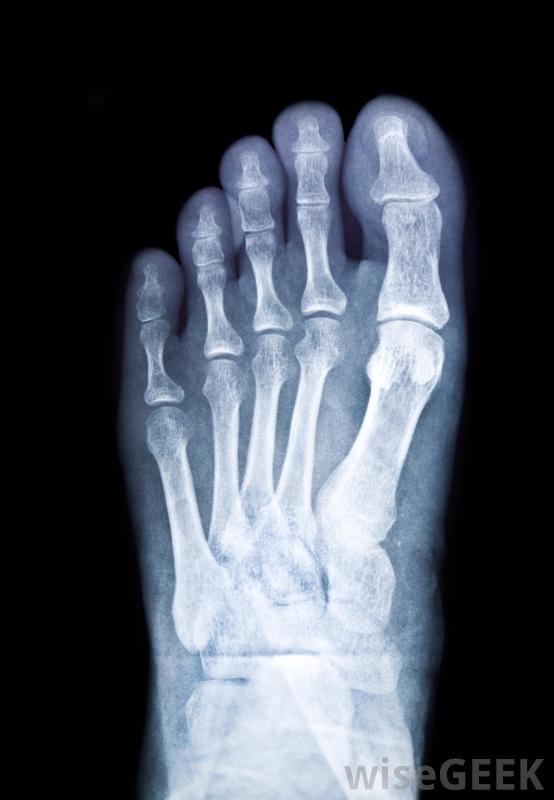

治疗断脚的第一步是脱下鞋子和袜子,抬起脚来。脚应该放在高于心脏的角度,以帮助减轻肿胀。你还应该在伤口上敷一层冰袋,但要注意不要直接放在皮肤上,通常在使用冰块前最好在脚上垫上毛巾,当脚抬高并有冰袋后,可以用夹板将其包裹在一个大枕头或毯子中医生通常会对骨折的脚进行x光检查,以确定损伤的严重程度。除了治疗骨折的基本步骤外,注意脚部或身体其他可能受伤的部位出血也是个好主意,只要出血不严重,一些轻微的压力和绷带可能有助于止血。在敷绷带之前,一定要先清洗伤口,这样你就可以看到伤口有多严重。抬起脚来减轻肿胀,还有助于阻止脚部出血治疗骨折的脚通常需要石膏。在骨折的脚用夹板固定,止血或减少后,您需要要么打电话给医务人员,要么把伤者送到急诊室如果伤势严重,你可能需要在做任何其他事情之前叫救护车来确保救援尽快到达。在大多数情况下,在去急诊室的途中或在你等救护车的时候,给伤者一些非处方止痛药是可以的。如果伤者大量出血,避免服用阿司匹林,因为这会导致血液变薄,从而导致更严重的出血抬起断了的脚直到能见到医生,这一点很重要。医生通常会做一些X光片来确定骨折的严重程度大多数情况下,脚会被放置在石膏里,病人需要使用拐杖来减轻脚上的重量,直到它愈合为止。骨折的脚愈合所需的时间通常取决于它的骨折程度。医生也可能会开一些止痛处方药。医生可能会进行随访到了脱模的时候,他或她就可以确定它已经正确地愈合了。应该给骨折的脚敷上冰袋脚骨折的患者需要使用拐杖将重量从脚上移开,直到痊愈治疗断脚的第一步是抬起脚。